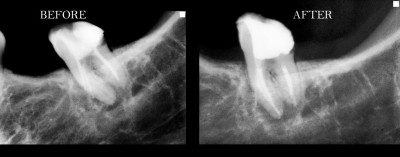

Περιστατικά